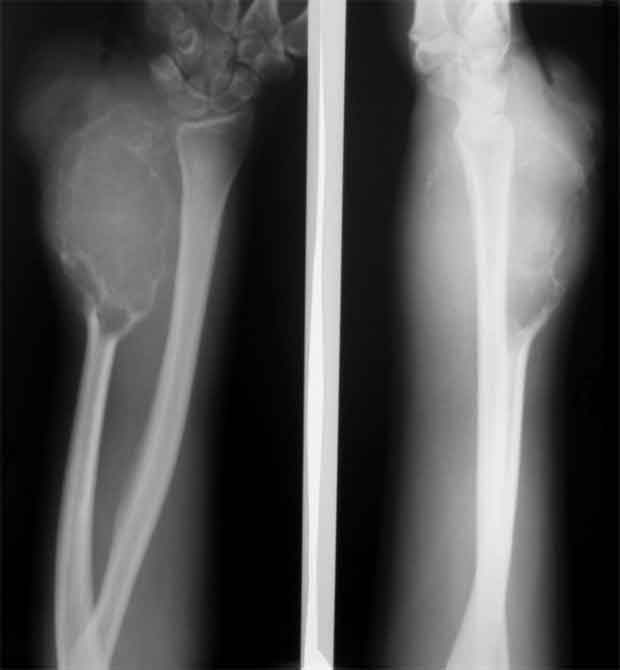

[Ortho] остеобластеокластома локтевой кости

Уважаемые коллеги, госпитализировали, наконец, эту пациентку, чему не очень рады, как клиническая, так и рентгенологическая картины изменились, кроме того Hb 76.Направил на повторную консультацию к онкологу. Остеобластеокластома может себя так вести?